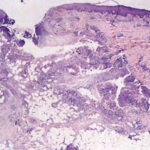

Histopathology . Pyoderma gangrenosum exhibits a dichotomous tissue reaction, showing central necrotizing suppurative inflammation, usually with ulceration, and a peripheral lymphocytic vascular reaction comprising perivascular and intramural lymphocytic infiltrates, usually without fibrin deposition or mural necrosis . Transitional areas show neutrophils in a loose cuff around the angiocentric lymphocytic infiltrates, defining a mixed lymphocytic and neutrophilic vascular reaction termed a Sweet’s-Iike vascular reaction . Bullous lesions may also demonstrate a Sweet’s-like vascular reaction with perivascular disintegrating neutrophilic infiltrates and hemorrhage without mural necrosis or luminal fibrin deposition. At variance with Sweet’s syndrome is destruction of the connective tissue framework with resultant tissue pathergy . Although a leukocytoclastic vasculitis may be observed in areas of maximal tissue pathology, pyoderma gangrenosum does not reflect a primary vasculitis . In some cases a necrotizing pustular follicular reaction may be the central nidus of the lesion, particularly in the vesicular pustular variant associated with ulcerative colitis or hepatobiliary disease. In the superficial granulomatous variant, florid pseudoepitheliomatous hyperplasia may be observed along with the intraepithelial and superficial dermal suppurative granulomatous inflammation with admixed plasma cells and eosinophils . Gases of pyoderma gangrenosum associated with Grohn’s disease may have areas of granulomatous inflammation . |